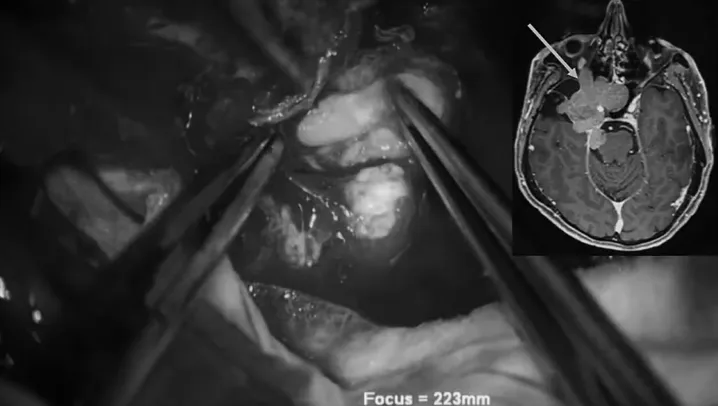

显微镜外科手术分步取出肿瘤图解

▼前内侧三角部位肿瘤切除

▼蝶窦部位肿瘤切除

▼内镜辅助阶段

显微手术切除肿瘤后,内镜辅助下切除在蝶窦内的肿瘤残体和粘膜。应用自体脂肪和纤维蛋白胶对硬脑膜进行水密封闭。